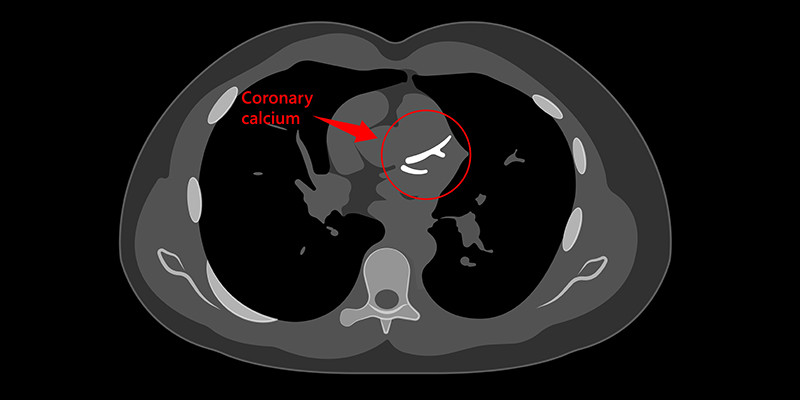

Moeten alle patiënten met (a)typische klachten van stabiele angina pectoris naar de cardioloog verwezen worden voor aanvullende diagnostiek? Het CONCRETE-onderzoek wil nagaan of een CT-scan met coronaire kalkscoremeting via de huisarts een adequaat alternatief kan zijn.